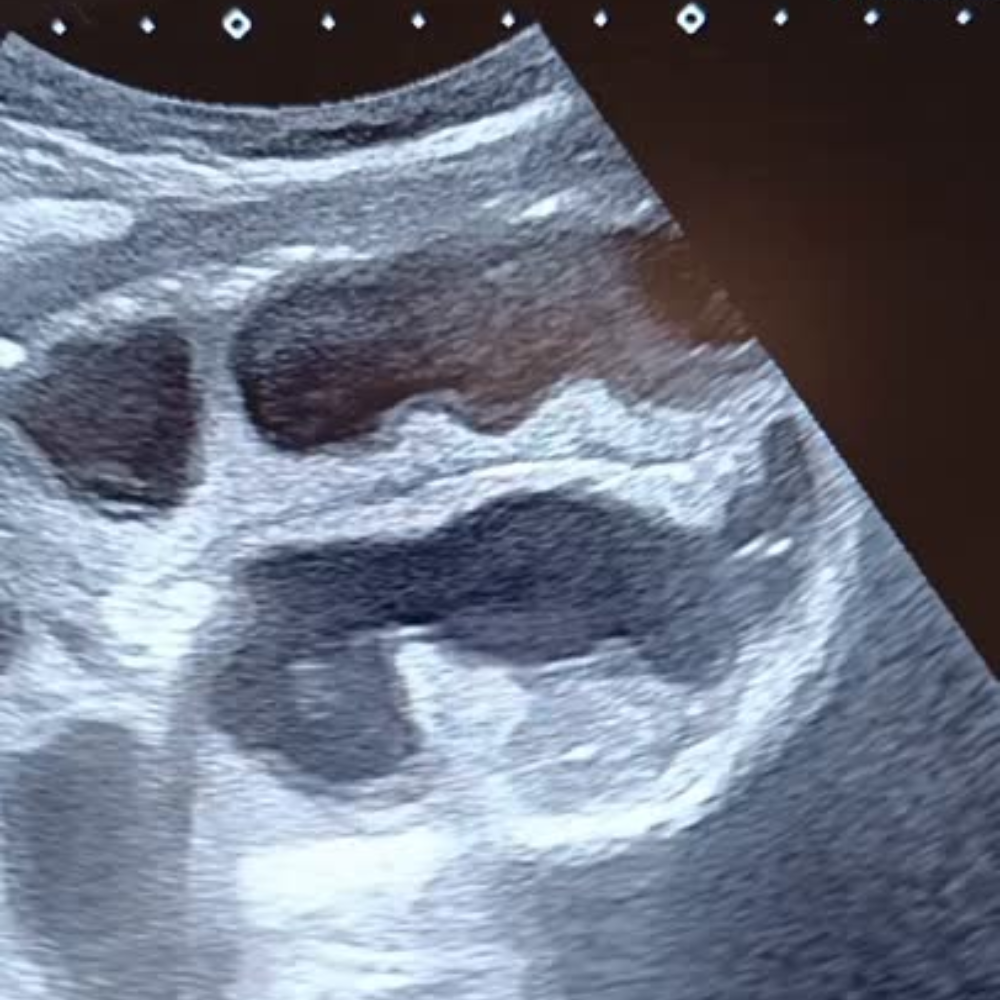

- Dilatation des anses grêles : diamètre > 25 mm (> 2,5 cm), contenu liquidien, paroi fine.

- Anses coliques : plus périphériques, contenu gazeux, haustrations visibles.

- Signe du tourbillon : mouvement de va-et-vient du contenu intestinal.